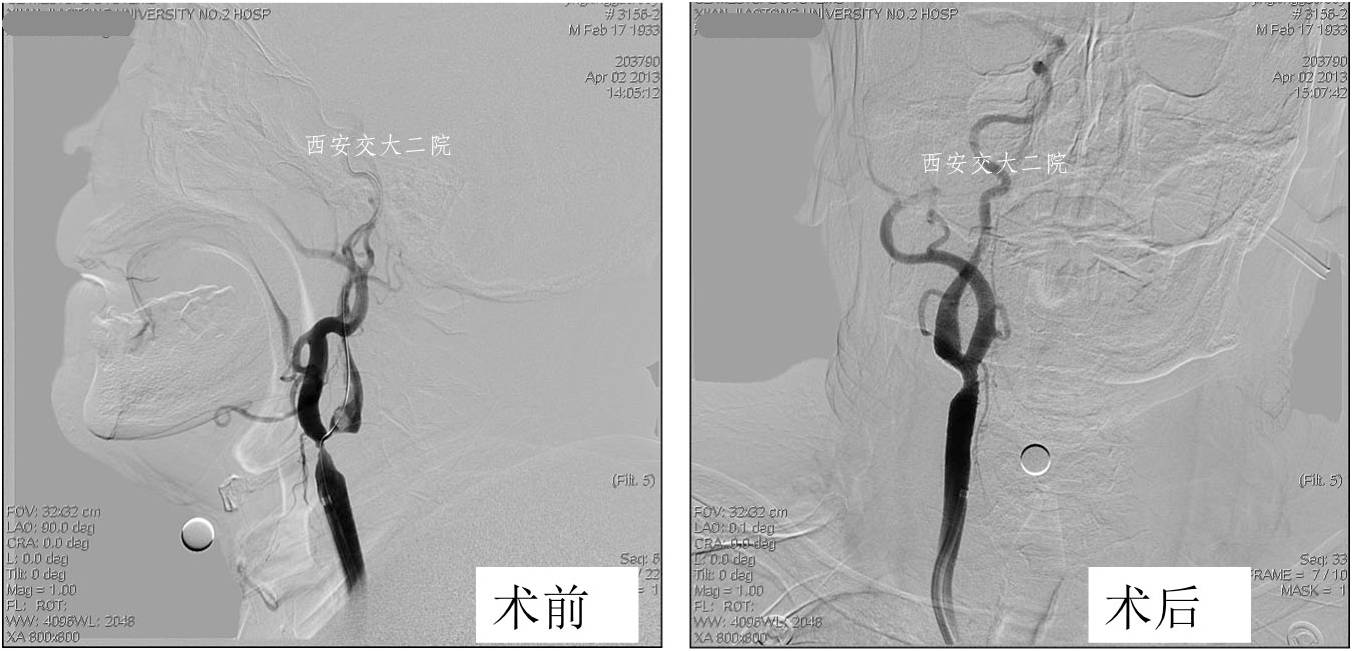

Case 1 基底动脉取栓 (2013年)

》35岁,女性;

》剖宫产后4天,右侧肢体活动不灵,言语不清13小时入我科。入科后3小时病情逐渐加重。

术前DSA

术后DSA